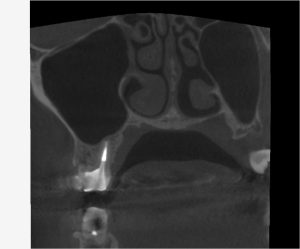

(術後6ヶ月のレントゲン、CT)

今回は全ての根管において、治癒が認められた。

治療前の症状も全て改善され、最終補綴へ移行した。